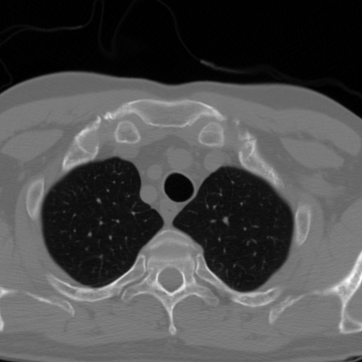

Figure 3 shows an example of a single frame of the reconstructed MR image sequences for an acceleration factor of using several approaches. We show the reconstructions that correspond to the single scalar parameter as well as to the scalar parameter pair (one spatial and one temporal) which are the parameters that maximize the PSNR of entire cine MR image and are obtained via a grid search by making use of the corresponding ground truth image. We also show the results that correspond to the parameters and which are respectively the single and the pair of scalar parameters that on average maximize the PSNR over the training set. These were obtained by treating the scalar regularization parameters as trainable parameters and training them by minimizing (33). We finally show the results for our estimated parameter-map with the proposed method. As observed, for all choices of the regularization parameters, the error with respect to the target image was significantly reduced compared to the initial zero-filled reconstruction. Further, we can see how the use of the estimated parameter-map yields the most accurate reconstruction and the best preservation of image details.

Figure 4 summarizes the results obtained over the test set with the help of box-plots. Compared to the initial zero-filled reconstruction, an improvement is clearly visible for all choices of the regularization parameter with respect to all reported measures and for all acceleration factors. In addition we see how allowing the temporal direction to be differently regularized than the two spatial dimensions positively influences the results compared to having one global parameter (orange vs blue). Last, we see how using the proposed method to estimate an entire spatio-temporal parameter-map further surpasses the scalar regularization parameter-maps (green vs orange and blue), especially in terms of SSIM. Table 1 lists the mean and the standard deviation of all TV-reconstructions. The results are consistent with the ones from the box-plots.